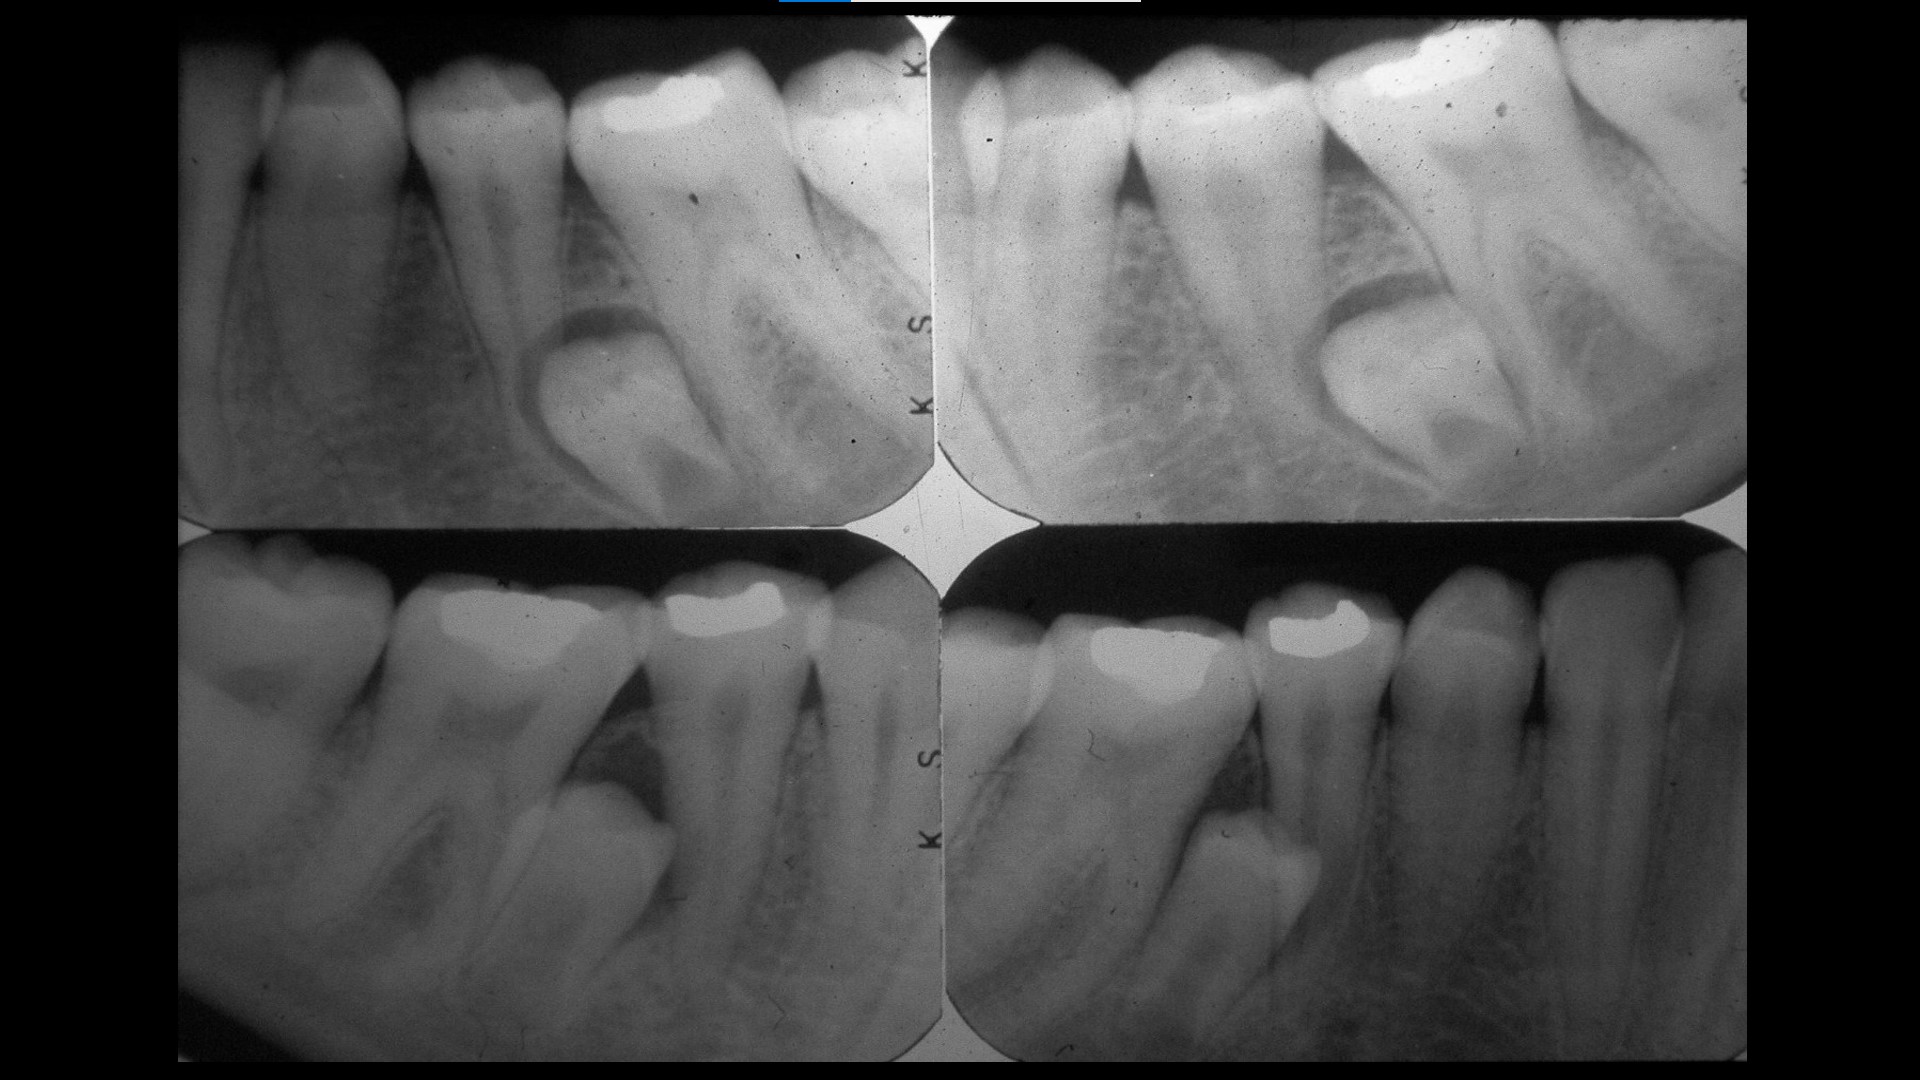

Impacted teeth